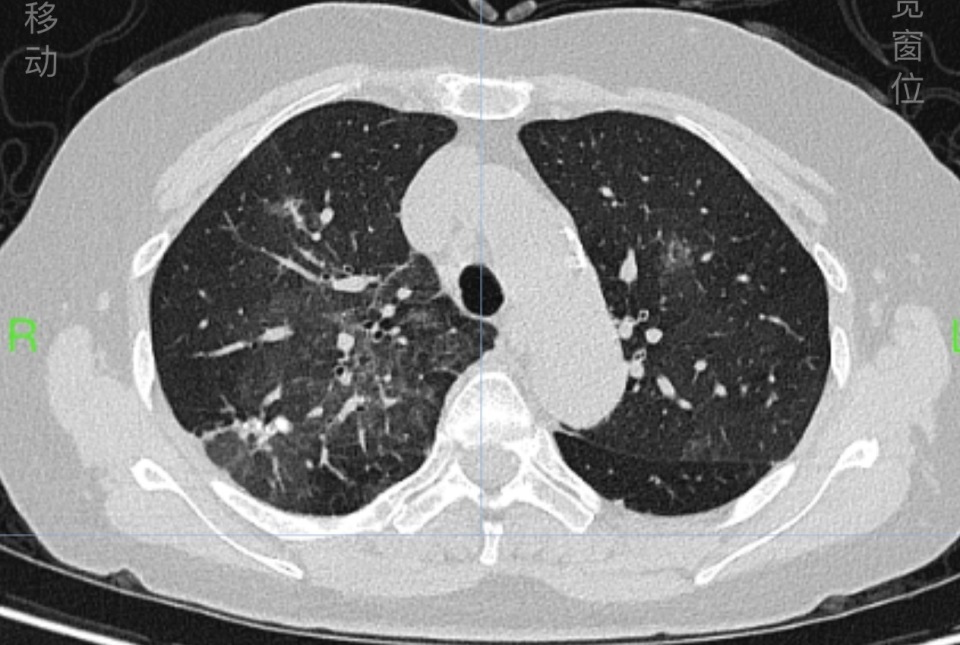

63岁的戴女士被诊断为重度过敏性哮喘多年,平时规律接受哮喘治疗,控制得不错。但近4天来,她出现发热、喘息发作厉害,夜间憋闷不能入睡,于是赶紧到湖南省人民医院呼吸内科检查,发现双肺大片磨玻璃及网格样炎症病变。

△戴女士入院时肺部CT显示双肺大片磨玻璃及网格样炎症病变(上图),治疗一周后的肺部CT如下图